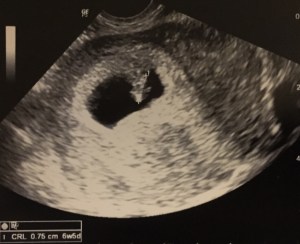

Things have changed so much between when I was your age (and by “your age” I mean 47 days in the oven) and now. My first photo is one from the hospital after I was born; the same can be said for your mom and all of your aunts and uncles. YOUR first photo was taken today, 47 days into your development. You just might be the cutest splotch of white I’ve ever seen on paper…I can see your mother’s resemblance in you.